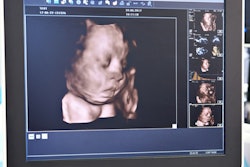

Bump for Joy opened in June 2019 in Prairieville, LA, as a "gender reveal, maternity, and children's boutique that also offers spray tanning." The center offered 2D, 3D, and 4D ultrasound scans to pregnant women, and it pointed out that it could determine the gender of babies at 13 weeks gestation.

Bump for Joy also offered a "Baby Blues Package" for expecting mothers who had experienced loss, had a miscarriage, or had infertility issues. The package included an ultrasound scan once a week for 15 minutes, according to news reports of the center's opening. Scans were performed by owner Riley Dunaway, who told reporters she had "completed a course" and had two years of supervised training in ultrasound.